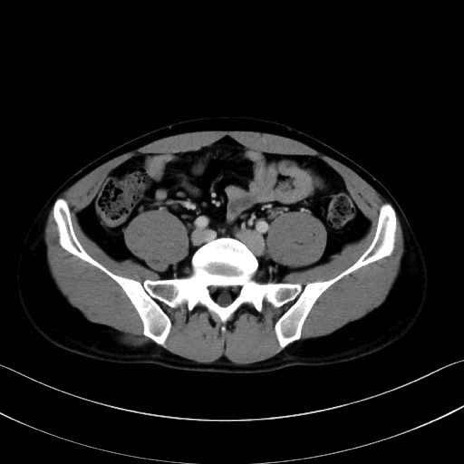

小殿筋 (Gluteus minimus)